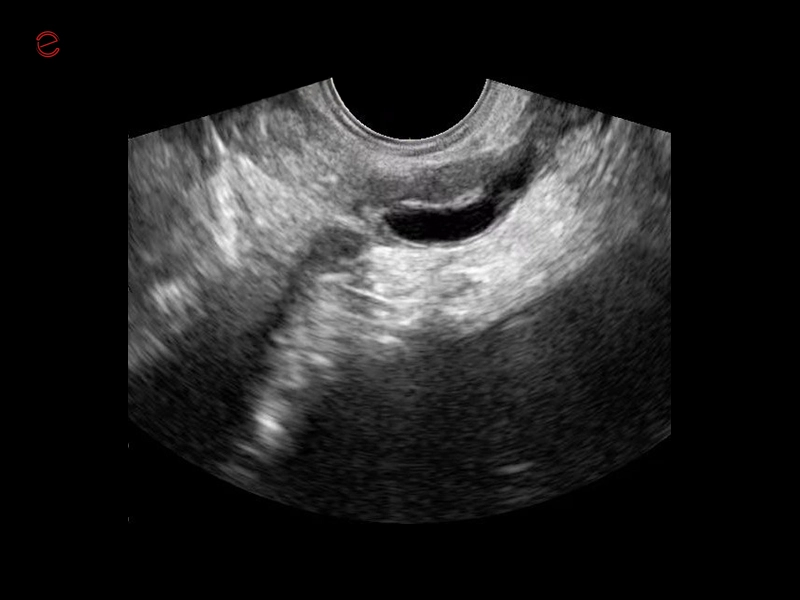

Q7 - WH Uterus

Q7 - WH Uterus